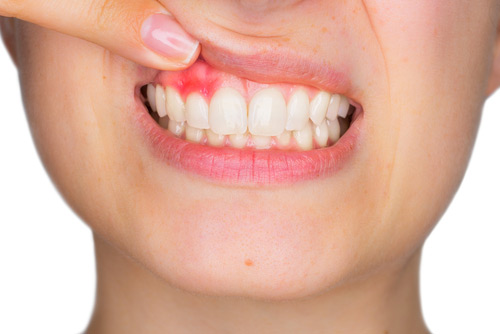

- отечность и болезненность слизистой рта;

Острая форма заболевания постепенно переходит в хроническую, когда периоды обострения сменяются относительно спокойными и комфортными стадиями. При хроническом остеомиелите челюсти у пациента часто находят свищи, откуда выделяется гной. Отечность и подвижность зубов, а также увеличение лимфатических узлов тоже присутствуют. Причем необязательно, что на этапе ремиссии боль сохраняется — у некоторых пациентов она полностью отсутствует, а возвращается с очередным обострением. Но в этом случае болевой синдром может возвращаться по нарастающей — то есть усиливается с каждым разом.